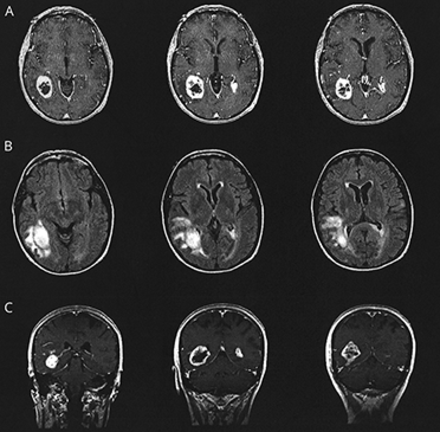

教学实验:未能看到血在瑞士

这张图片表明,急性出血可能不会出现在susceptibility-weighted成像,以前一直认为是非常敏感的血液。